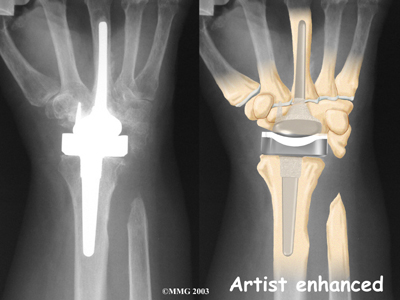

Modern artificial wrist joints are made of metal and plastic. The part that fits against the end of the radius bone of the forearm is called the radial component. It is made up of two pieces. A flat metal piece is placed on the front part of the radius. It has a stem that attaches down into the canal of the bone. A plastic cup fits onto the metal piece, forming a socket for the artificial wrist joint.

The part that replaces the small wrist bones is called the distal component. This piece is made completely of metal. It is globe shaped to fit into the plastic socket on the end of the radius. The metal distal component is attached by two metal stems that fit into the hollow bone marrow cavities of the carpal and metacarpal bones of the hand.

The plastic used in artificial joints is tough and slick. It allows the two pieces of the new joint to glide easily against each other as you move your wrist. The ball and socket allow movement of the wrist in all directions.

The hand bones and the radius bone of the forearm are then prepared with special rasps. The rasps are used to:

Bore Holes

in the bone for the metal stems of the:

Replacement Joint

The surgeon will take some time to get the stems to fit tightly. The joint is put in place and tested through its range of motion to make sure it moves correctly. Once the surgeon is satisfied with the fit, the stems of each metal implant are:

Cemented into Place